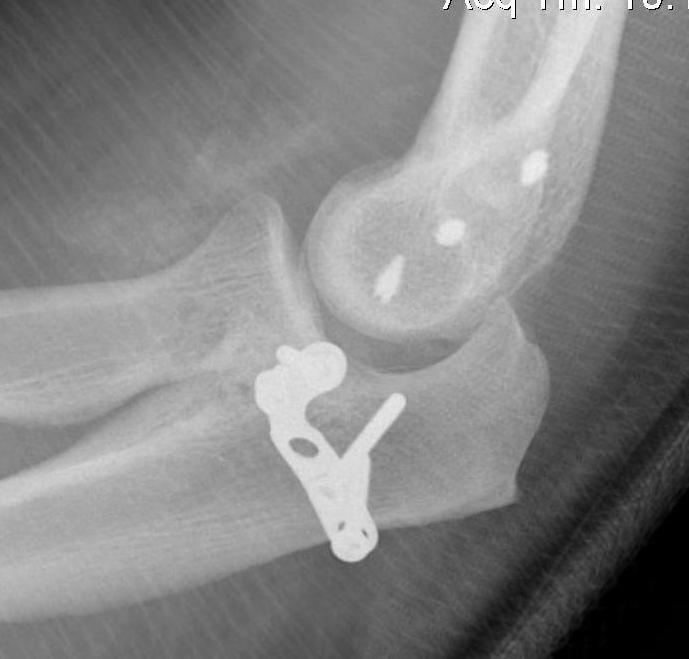

coronoidCoronoid Buttress Plate AP

Medial approach and buttress plate with LCL repair

buttress plate

Universal posterior approach with radial head replacement and medial approach with medial buttress plate